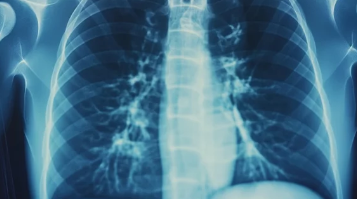

결핵은 흉부 X-ray 검사, 객담 검사, 결핵균 PCR 검사 등을 통해 진단할 수 있습니다.

- 흉부 X-ray 검사: 폐결핵 여부를 확인하기 위해 흉부 X-ray 검사를 시행합니다. 흉부 X-ray 검사에서 이상 소견이 발견되면 추가 검사를 시행합니다.